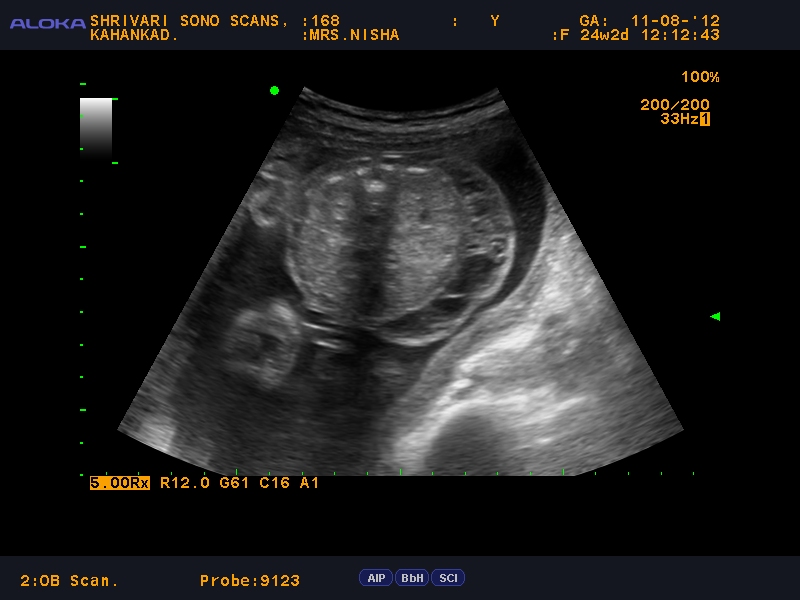

First trimester ultrasound (12 weeks), axial plane at cranium base.

The patient had a history of 12 weeks amenorrhea which corresponded with the age of the fetus on the ultrasound scan.

Cystic hygromas may also have an infiltrative appearance and may be uni or multilocular. This ultrasound finding is seen in fewer than 1 out of 100 pregnancies. Of hg) and her other vital signs were normal. Something called a cystic hygroma.

The prenatal diagnosis of cystic hygroma using ultrasound is well documented in the literature. Show 3 previous comments violation reported Her blood pressure was normal (bp: We are devasted and don't understand.